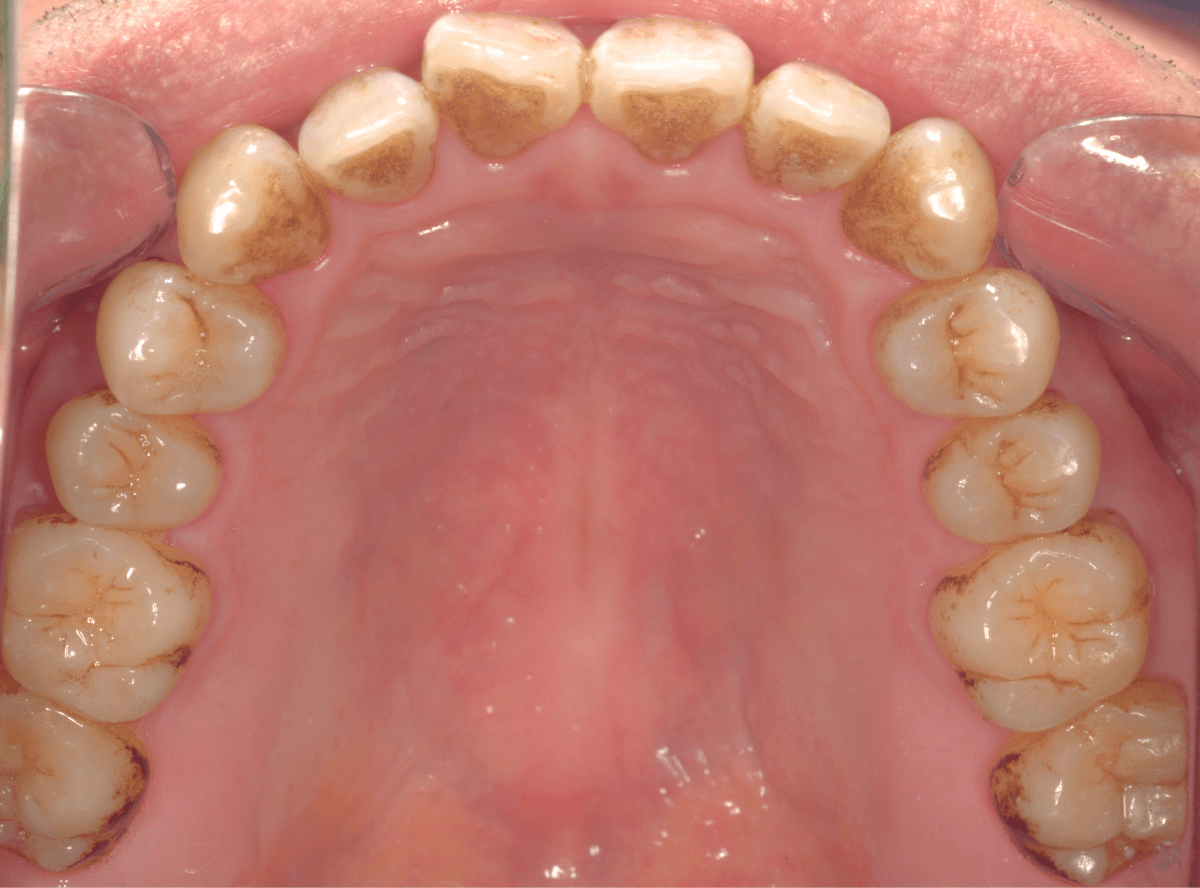

Case.2

検査と歯石除去を希望されて来院された患者さんです。

歯石と着色が歯の裏側まで広範囲についていましたので、まず、通常の歯周病処置である、歯石除去や歯ブラシ指導を行った後に、仕上げにビューティークリーングで仕上げを行いました。